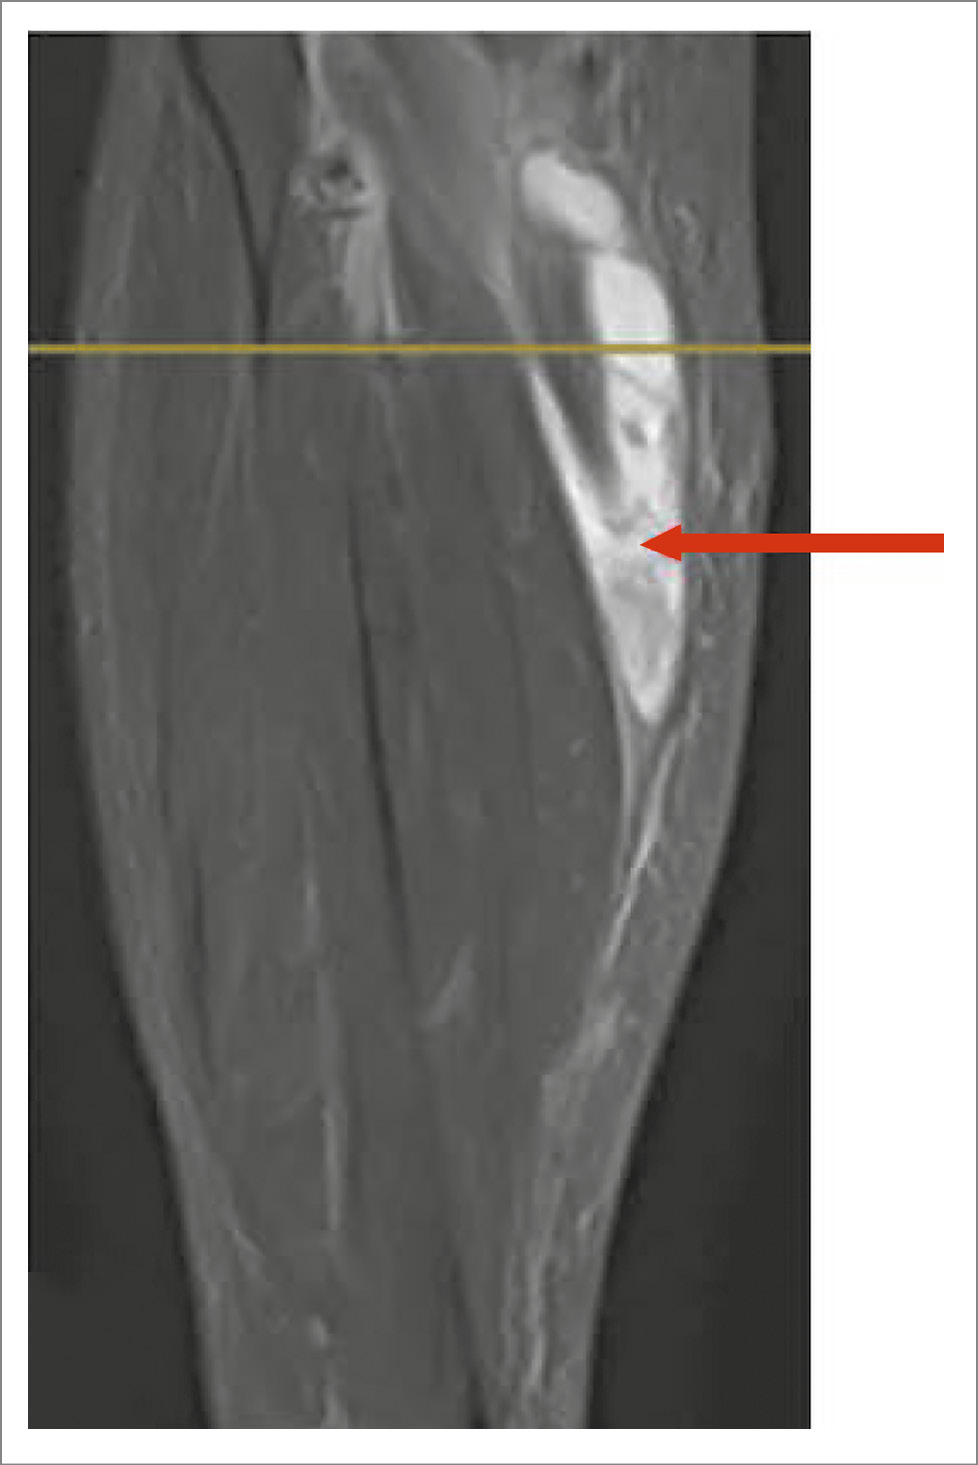

На МРТ разрыв КБ визуализируется как истечение жидкости в межмышечные пространства (рис. 3–5).

Рис. 4. МРТ голени, коронарный срез, Т2-ВИ STIR. Разрыв КБ, сепарация подкожной клетчатки истекающей жидкостью (красная стрелка).

Рис. 5. МРТ голени, коронарный срез, Т2-ВИ STIR. Разрыв КБ, истечение жидкости в межмышечное пространство голени (красная стрелка).